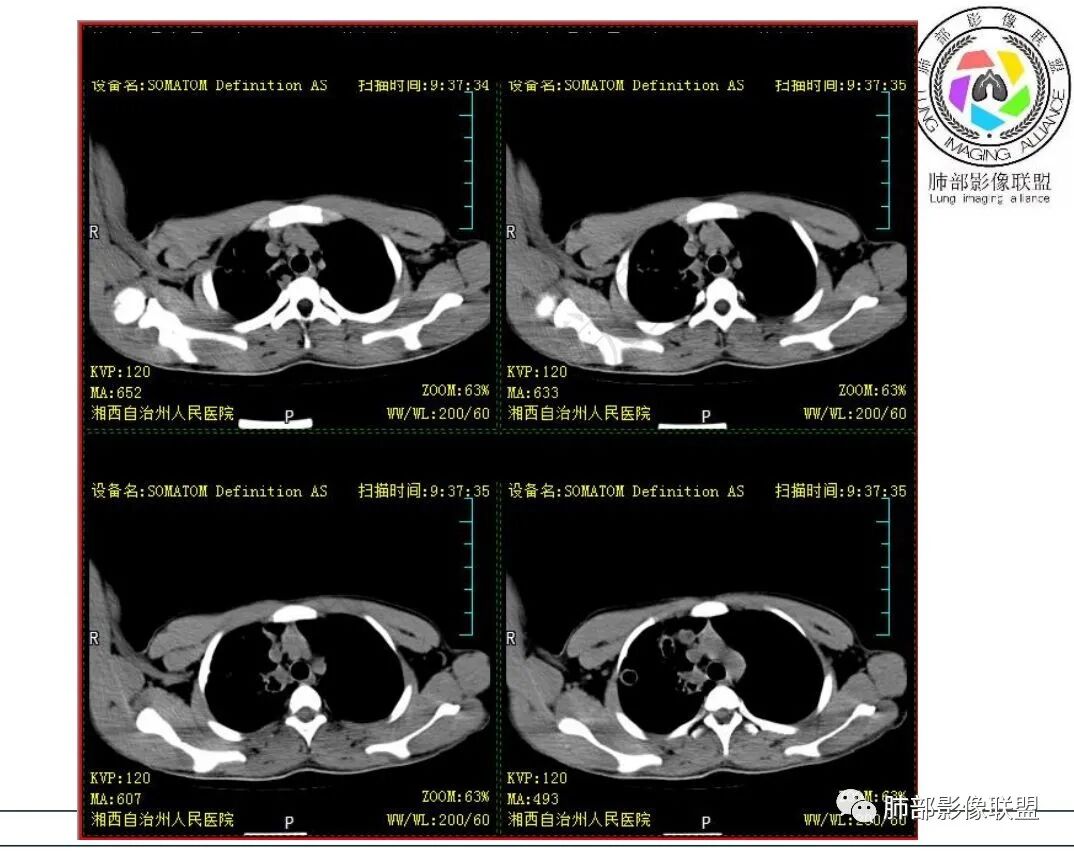

影像:右肺上叶多发实变影结节影,边界模糊,边缘收缩,伴多发空洞,洞壁光滑,部分支气管壁增厚。

3.首次CT提示:右肺上叶多发结节影及实变影,簇状分布,周围散在磨玻璃影,结节内多类圆形空洞,内壁光整,有一定张力,偶见液平。部分支气管壁增厚。

考虑良性感染性病变可能。